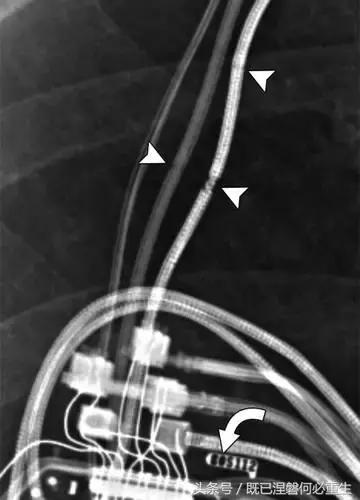

造成设备故障的最常见的X光检查原因之一是铅断裂。锁骨下静脉经过锁骨下的部位是骨折最常见的位置[16](图7A和7B)。在这个位置的损伤可能发生在导管或导线,并已被描述为锁骨下夹断综合征和锁骨下压溃综合征[16?18]。临床上,骨折的导线通常在患者中产生能够是连续的,间歇的或依赖于患者定位的症状。识别这些状况可能需要挑衅性的动作,例如等长臂锻炼,仰卧或侧向定位或Valsalva。设备检查将显示异常的起搏阻抗(如果绝缘破裂允许导体暴露则减小,如果导体断裂但绝缘完好则增加),感测错误和起搏捕获损失[12]。导线断裂或绝缘损坏可能导致感测或起搏异常。对心律失常的不适当的过感知或欠感应可能导致不适当的治疗,例如抗心动过速起搏和休克治疗,或不适当的抑制治疗。

用于将导线的近端部分固定到胸壁的导线固定件能够模拟损伤。扎带是通常位于锁骨和发生器之间并且能够压接引线的套囊(图8A和8B)。熟悉这种外观和通常的射线透射束缚的位置能够防止错误报告磨损的线索。

图。 8A在两个不同患者中电极断裂的电极结合物的实例。

图。 8B在两个不同患者中电极断裂的电极结合物的实例。